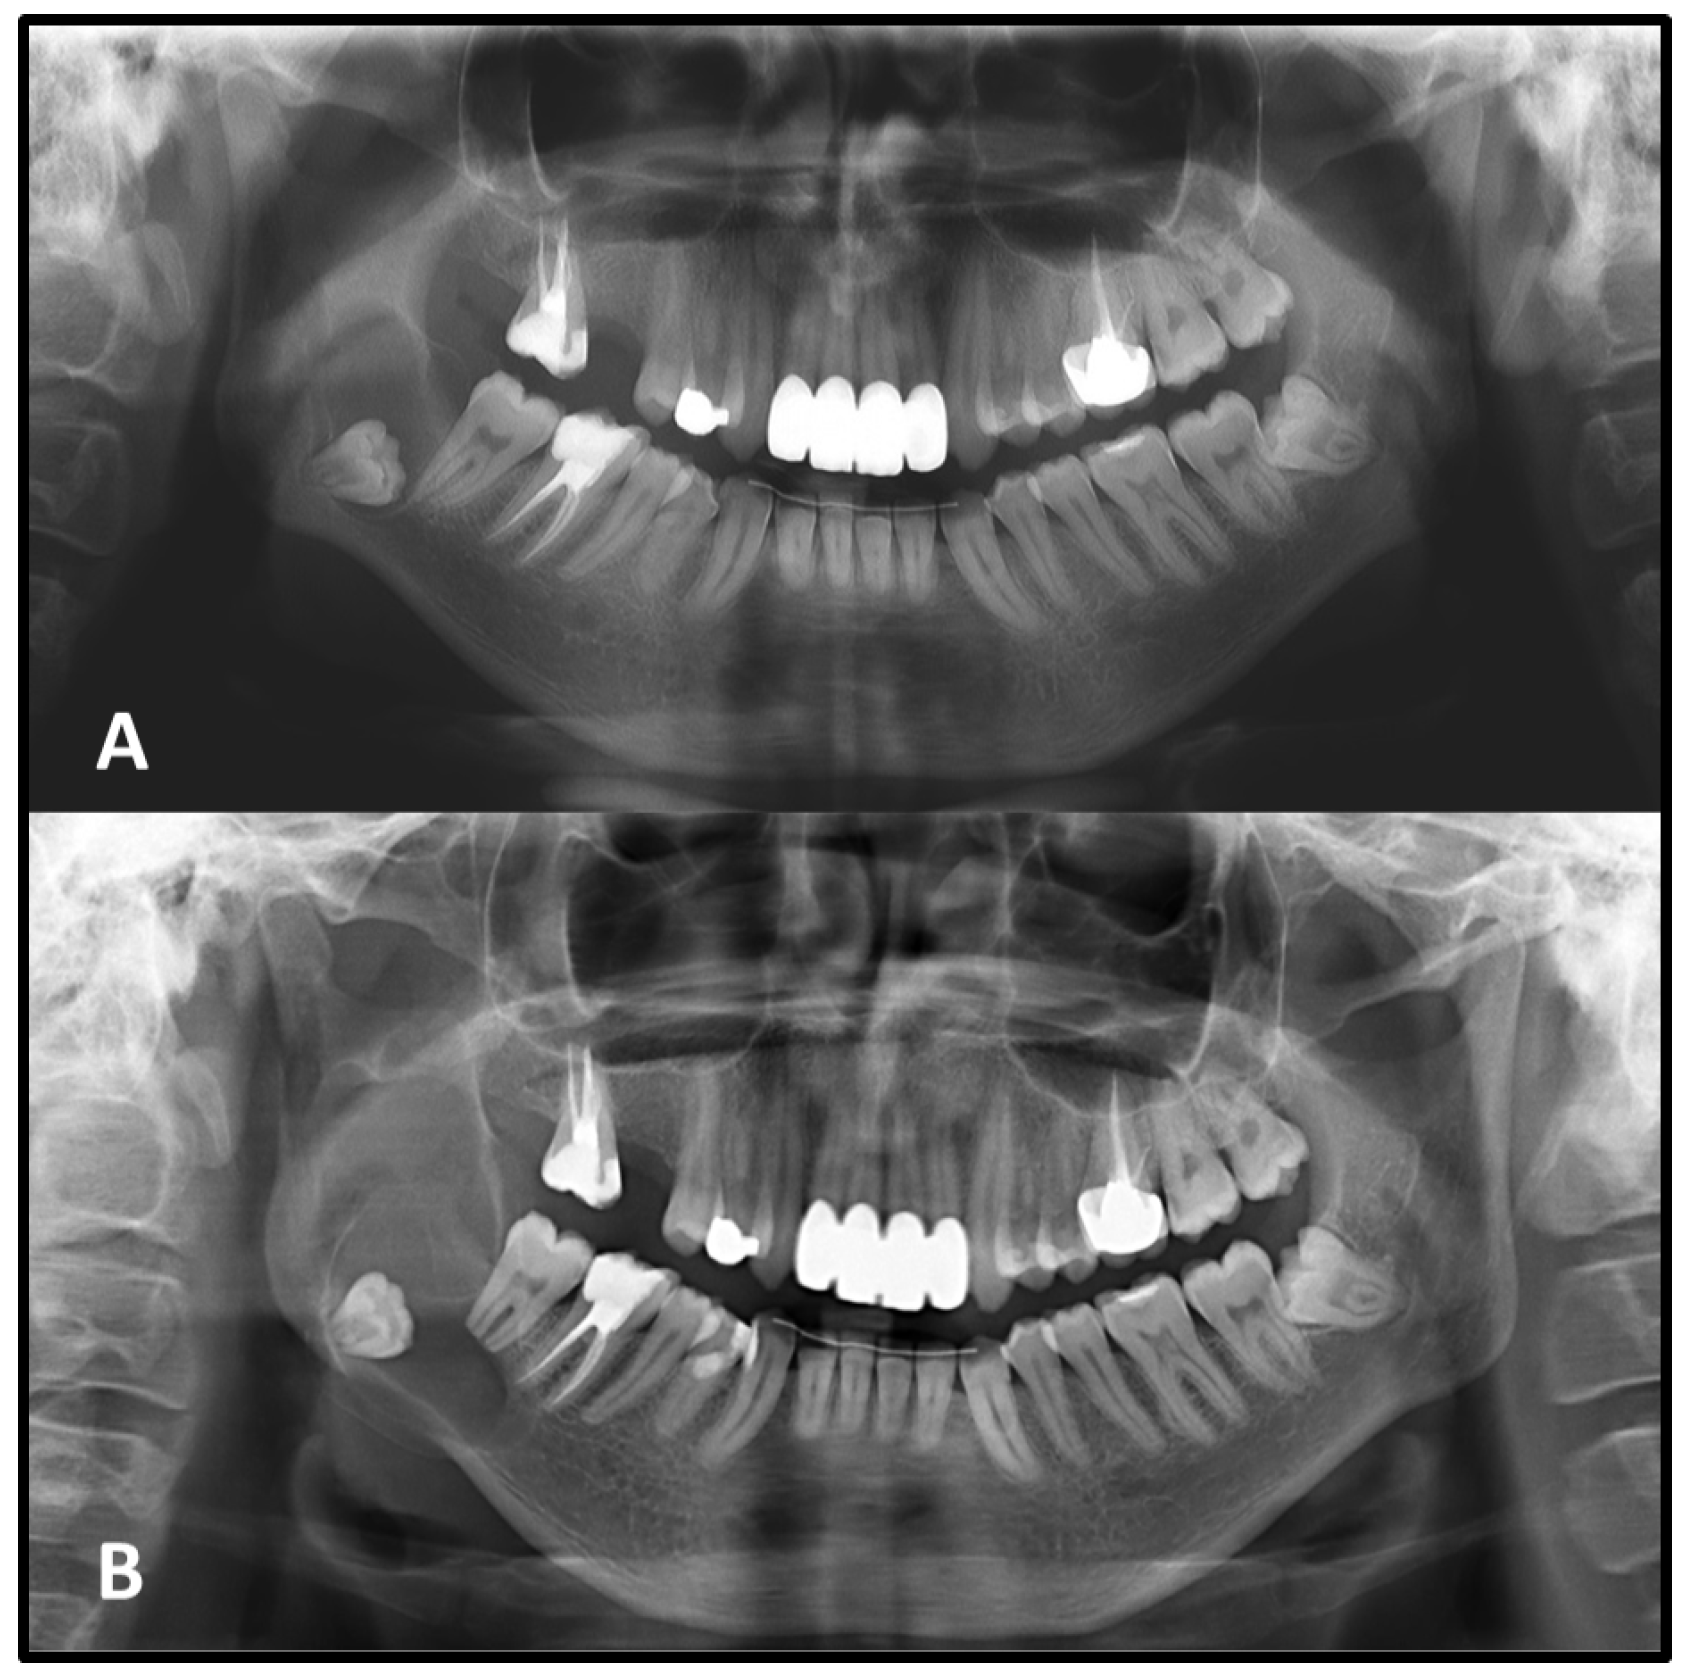

Changes in the relationship between the lesion and adjacent anatomical structures were observed during follow-up. Seventeen lesions that initially showed no proximity to the IAC and 2 lesions unrelated to the IC on the first radiograph were later found to exhibit radiographic contact with these critical neurovascular structures in the second image, a clear radiographic association with these anatomical structures was observed. This shift suggests a possible extension of the lesion toward critical neurovascular pathways over time (

Figure 5).

Cysts may displace the inferior alveolar nerve canal in an inferior direction or invaginate into the maxillary antrum [

5]. In the present study, some lesions that initially had no radiographic contact with the inferior alveolar canal (IAC) in the mandible and the incisive canal (IC) in the maxilla were found to encroach upon these anatomical landmarks in the later radiographs. As lesion boundaries expand, they may gradually approximate or compress adjacent anatomical structures, potentially increasing the risk of neurosensory disturbances or complicating future surgical interventions [

7]. These findings underscore the dynamic nature of seemingly indolent lesions and highlight the critical role of radiographic surveillance, not only for monitoring dimensional changes but also for evaluating evolving anatomical relationships that may influence both prognosis and treatment planning.